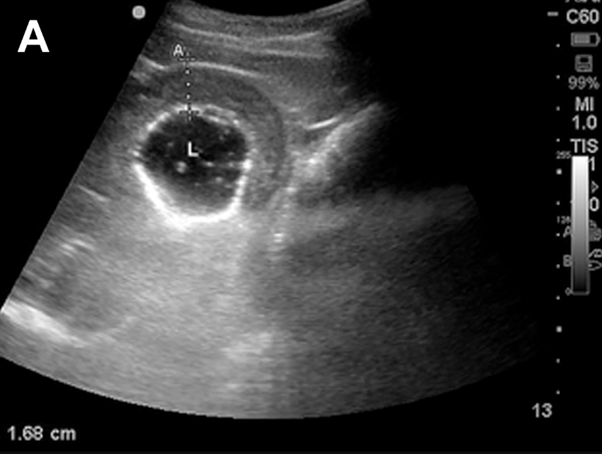

Thickened Small intestine ultrasound

Ultrasound image showing thickened small intestine (normal 3mm)

Ultrasound examination revealed significant thickening of the small intestine, and this, combined with the clinical picture, development of diarrhoea and faecal testing, led to a diagnosis consistent with Lawsonia infection. This condition, caused by the bacterium Lawsonia intracellularis, results in inflammation and thickening of the intestinal wall, which in turn affects nutrient absorption and protein levels.